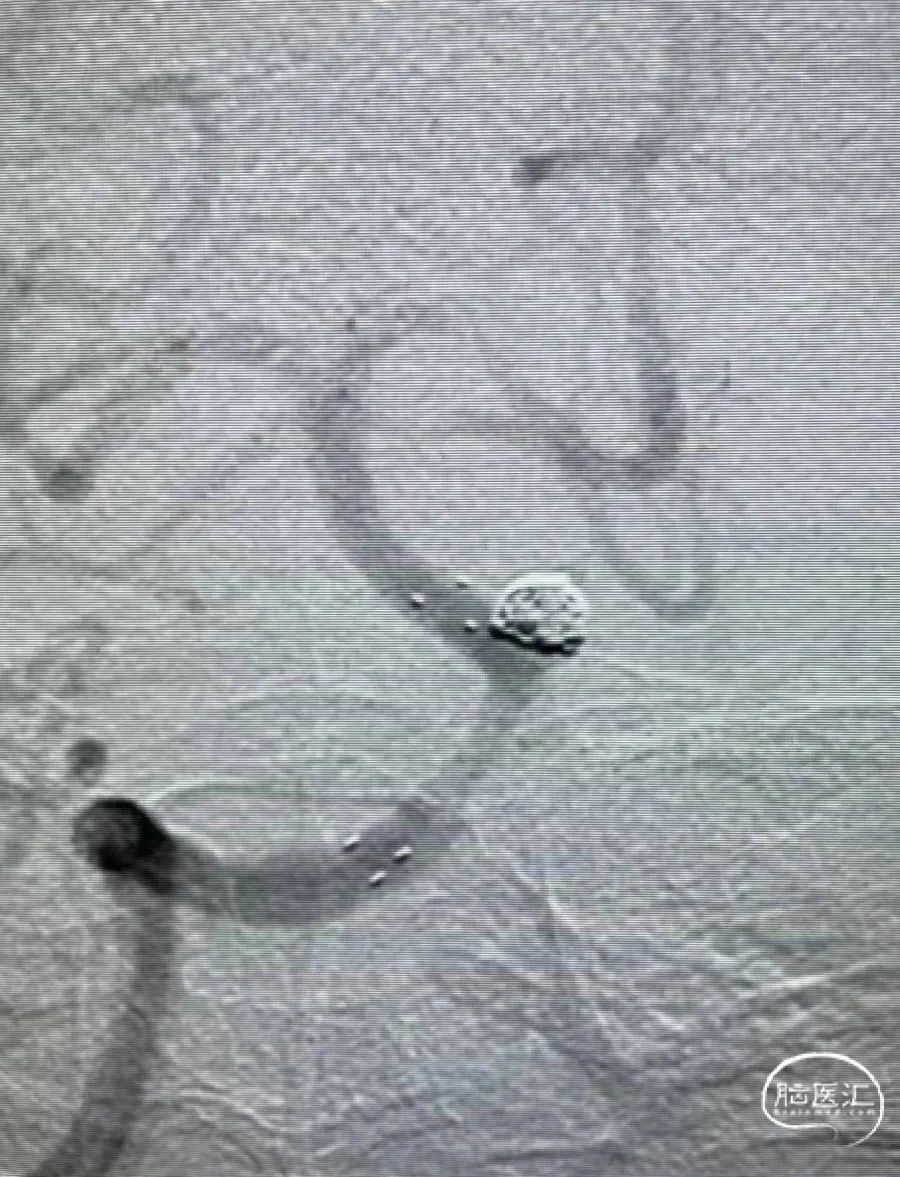

术后即刻影像

术后三个月复查影像

术后即刻影像

栓塞过程及术后影像